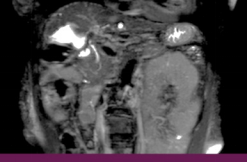

Ø 术前影像学检查

肝 S2 段及肝 S4 段见类圆形 T1WI 低、T2WI-SPAIR/DWI/ADC 高信号,较大者长径

约 10mm,界清。

T2 SPIR 冠状位